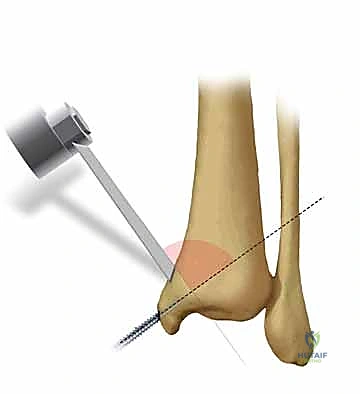

* مسامير التيتانيوم المجوفة (Cannulated Screws): مسامير قوية جداً يتم إدخالها عبر العظم لضغط أجزاء الكسر معاً.

* المسامير بدون رأس (Headless Compression Screws): تُستخدم في المناطق المغطاة بالغضروف، حيث تُدفن بالكامل داخل العظم لكي لا تحتك بالمفصل وتسبب تآكلاً.

يتم وضع المسامير عادة من اتجاهين (من الأمام للخلف، ومن الخلف للأمام) لإنشاء هيكل ميكانيكي صلب يتحمل الضغوط.